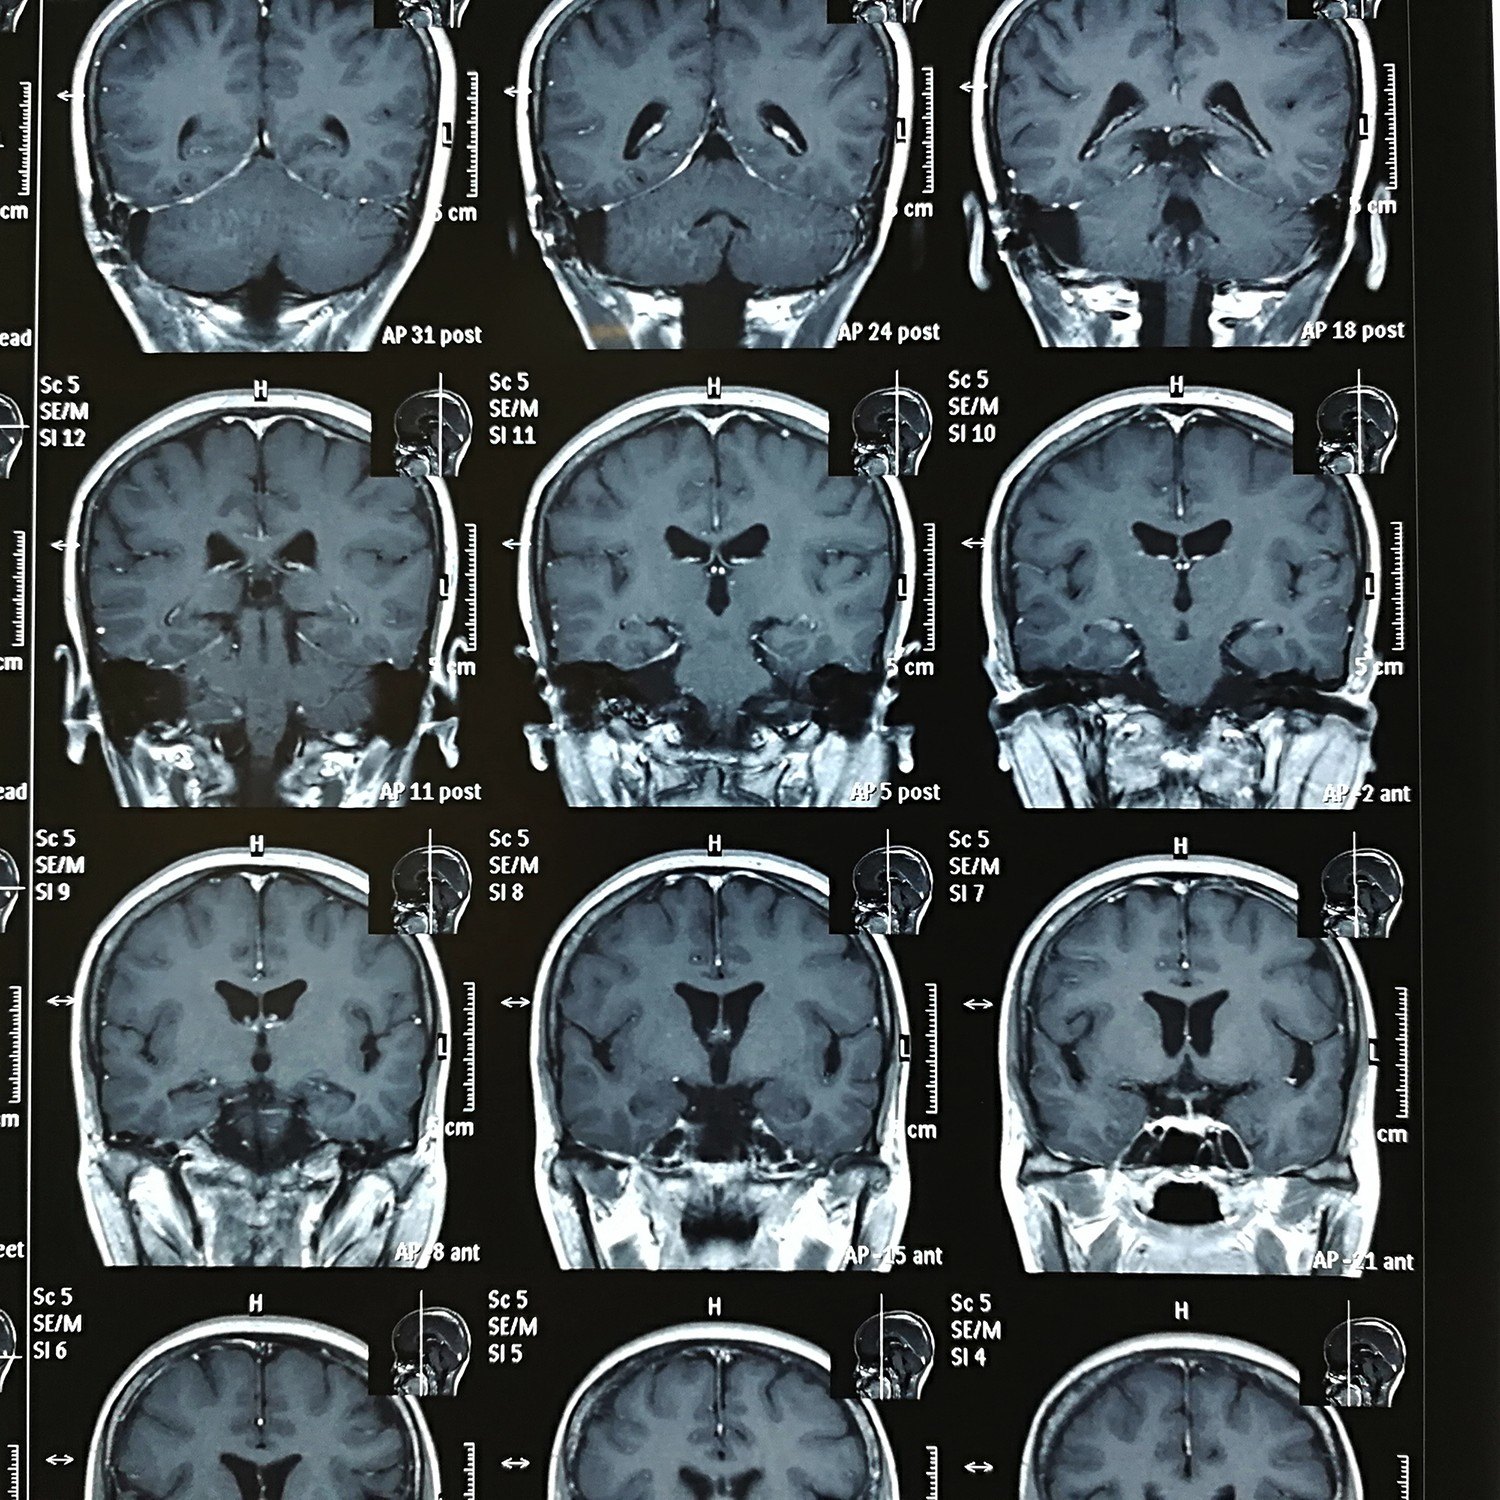

听神经瘤的诊断与治疗

图片尺寸943x980